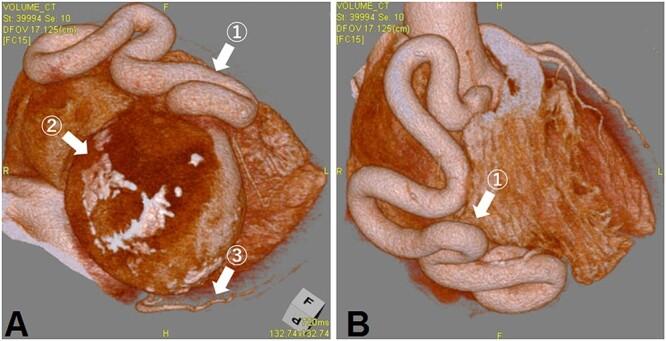

A rare case of giant coronary artery ectasia associated with coronary artery aneurysm was recognized. A 69-year-old woman presented with an ischemic electrocardiogram changes during a medical check-up. Coronary computed tomography angiography showed right coronary artery (RCA) ectasia associated with a giant aneurysm originating from the distal RCA. She was asymptomatic and exhibited no risk factors, including Kawasaki disease, hypertension, diabetes mellitus or family history. The patient underwent surgery for giant coronary aneurysms to prevent rupture. The aneurysm was on the peripheral side of the right coronary artery; hence, coronary artery bypass was not performed. The patient's postoperative course was uneventful. Histopathological examination of the aneurysm revealed degeneration due to atherosclerosis. She was prescribed warfarin and aspirin for thrombus prevention.

一例罕见的巨大冠状动脉扩张合并冠状动脉瘤被确诊。一名69岁女性在体检时出现缺血性心电图改变。冠状动脉计算机断层扫描血管造影显示右冠状动脉(RCA)扩张,伴有一个起源于RCA远端的巨大动脉瘤。她没有症状,也没有包括川崎病、高血压、糖尿病或家族史在内的危险因素。患者接受了巨大冠状动脉瘤手术以预防破裂。动脉瘤位于右冠状动脉外周侧;因此,未进行冠状动脉搭桥术。患者术后恢复顺利。动脉瘤的组织病理学检查显示为动脉粥样硬化性退变。她被开了华法林和阿司匹林以预防血栓形成。